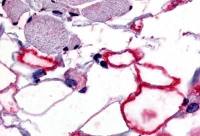

WB analysis of various sample lysates using GTX55561 CD5L antibody.

Dilution : 1:1000

Loading : 25μg per lane